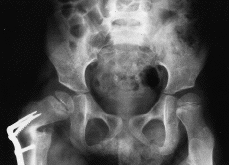

Figura 3. Ejemplo pre y postoperatorio tras la osteotomía, en una cadera derecha subluxada y con displasia acetabular, que por su edad se trató con una osteotomía de fémur.